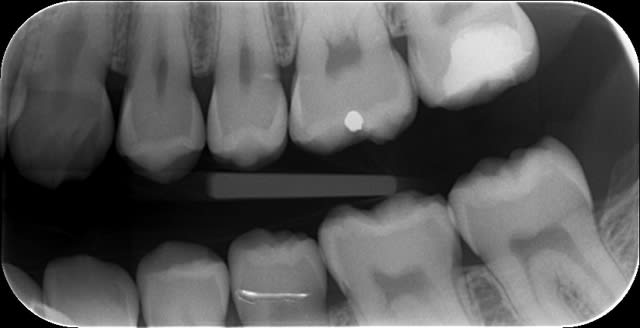

Une belle instrumentation en mésial, quelle tristesse.

Tout allait bien en progressant à patte de velours jusqu'à l'alésoir 30-4 trop fatigué apparemment (FKG Race), et j'ai donné un peu trop de force dans la progression verticale.

J'ai essayé de déloger la lime, j'ai cassé la deuxième puis la troisième.

Bon le canal est propre à défaut d'être étanche.